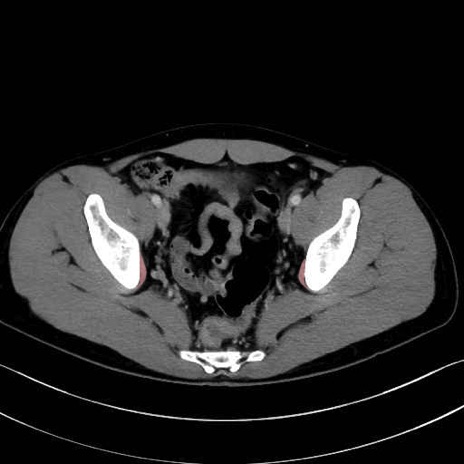

内閉鎖筋 (Obturator internus)